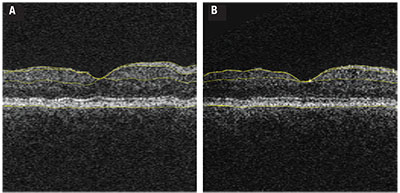

| Figure 1. Optical coherence tomography with segmentation performed in a fashion similar to that used in the longitudinal study analysis1 in a patient with diabetes at the outset of the longitudinal analysis (A) compared to the same patient at the final follow-up demonstrating the cumulative thinning over the study duration (B). Yellow automated segmentation outlines the internal limiting membrane, nerve fiber layer-ganglion cell layer boundary, inner plexiform-to-inner nuclear layer boundary and basement membrane. |

Our prospective study involved a cohort of 45 people with diabetes with no or minimal DR, following them with annual OCT analysis over an average of 73 months. Subjects had a mean HbA1c of 8.2 percent at baseline. We performed regular measurements of HbA1c, color fundus photography and OCT imaging. Subjects developed significant inner retinal thinning over the course of the study regardless of their DR status (Figure 1, page 33).

NFL thinning occurred at an average rate 0.25 μm/year; parafoveal GCL+IPL thinning occurred at a rate of 0.29 μm/year, after correction for age, sex, HbA1C status, DR status, blood pressure, DR progression and duration of diabetes. This thinning was statistically significant when compared to the normal age-related rate of thinning, and was readily apparent over the duration of the study (Figure 2).